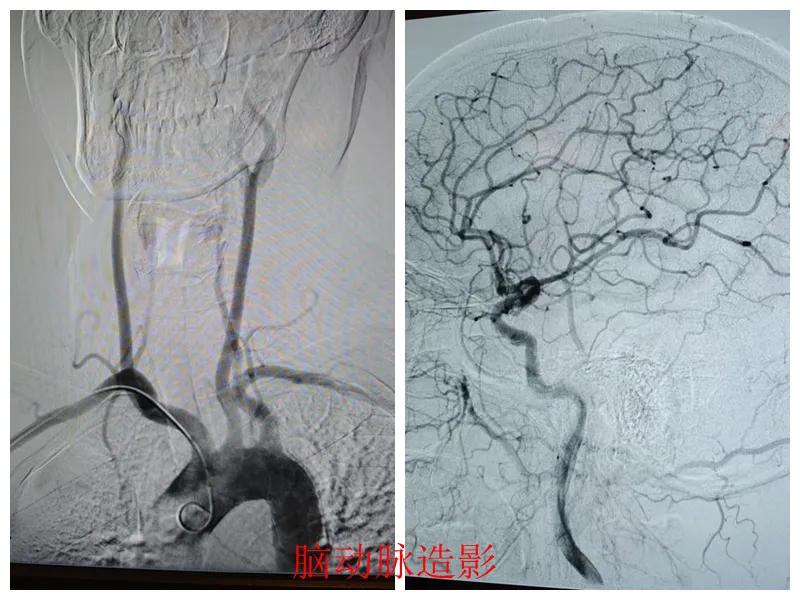

術(shù)前準(zhǔn)備完善后,在王瑾院長帶領(lǐng)下,心血管內(nèi)科主任李慧新、影像科主任宋貴良、副主任醫(yī)師趙進(jìn)科等緊密協(xié)作,成功為患者實施了冠狀動脈造影及腦動脈造影兩項檢查。冠狀動脈造影結(jié)果提示:患者右冠狀動脈慢性閉塞,腦動脈造影提示腦血管多支狹窄病變。